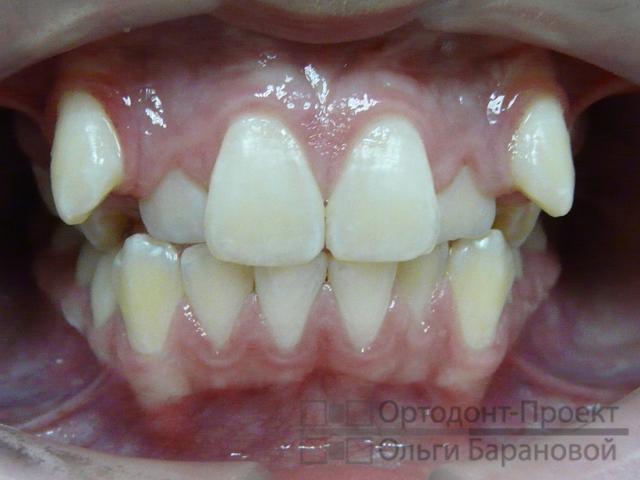

Фотометрия перед началом ортодонтической терапии:

Врач-ортодонт поставил диагноз: скученность зубов на верхней челюсти. Рекомендуется установка брекет-системы Damon, которая отличается наличием двух пазов в замке брекета. На одной из стадий терапии доктор применит две дуги: первая будет отвечать за движение клыков, а вторая – за фиксацию резцов, чтобы избежать их смещения под воздействием клыков. Металлические брекеты Damon представляют собой современное и оптимальное решение. Их главные преимущества заключаются в доступной цене, компактных размерах и высокой эффективности, при условии правильного расчёта со стороны врача.